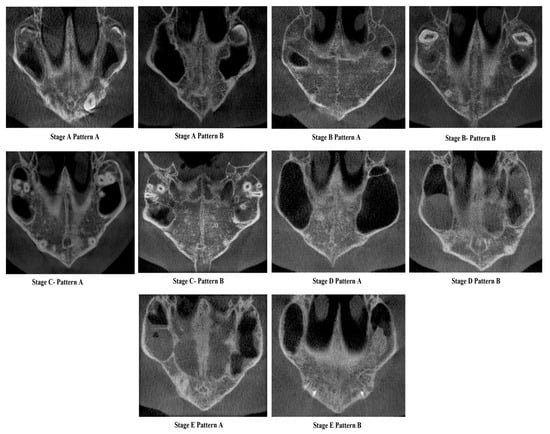

Stage A—Pattern A—Single, wide, continuous radiolucent linear space bounded by well-defined radiopaque lines extending from posterior palate anteriorly.

Stage A—Pattern B—Same as the previous standard classification Stage A—Single high-density relatively straight radiopaque (RO) line [2].

Stage B—Pattern A—Single straight high-density sutural line in the maxillary region, comparable to Stage A. The suture is single scalloped toward the palatal bone region.

Stage B—Pattern B—Equivalent to the previous standard classification Stage B—Single scalloped line of high-density radiopacity.

Stage C—Pattern A—Single scalloped line in the region of the premaxilla and toward the palate with two parallel RO lines with small radiolucent (RL) areas.

Stage C—Pattern B—Similar to the previous standard classification Stage C—Continuous or irregular-2 RO, non-scalloped or scalloped, parallel lines separated by low-density (RL) areas in the palatal and premaxillary region.

Stage D—Pattern A—Palatine suture (not completely fused)—50% or less than 50% fused in the posterior maxilla and continues anteriorly as two parallel radiopaque straight or irregular lines with radiolucent spaces, maxillary suture seen as two continuous or irregular RO lines or a single radiopaque line.

Stage D—Pattern B—Palatine suture—more than 50–100% fusion of posterior palatine region and continues anteriorly as straight or irregular lines with radiolucent spaces in between, maxillary suture seen as two continuous or irregular RO lines or a single radiopaque line.

Stage E—Pattern A—Palatine suture completely fused, but maxillary suture 50% or less than 50% fused and seen as two RO lines toward maxilla.

Stage E—Pattern B—Palatine suture completely fused and maxillary suture more than 50–100% or near complete fusion.

A validation study of the novel midpalatal suture maturational stages classification was carried out by three experienced investigators (C.S., N.A., F.A.): an oral radiologist, an orthodontist, and an oral pathologist. Each had more than five years of experience interpreting CBCT scans for research and diagnostic purposes. Prior to the study, the investigators were shown the definitions and illustrations (Figure 1 and Figure 2) of the maturational stages via a PowerPoint presentation against a black background. Calibration took place using ten images, where all investigators independently classified the sutures, followed by a discussion of the different stages. For the validation phase, 30 images—randomly chosen to represent all maturational stages—were classified blindly by the three investigators in a controlled, dimly lit environment, using the same high-definition monitor. The same images were randomly reordered and reclassified by the investigators two weeks later to assess intra-rater reliability.

Figure 2. Cone Beam Computed Tomographic images of the New classification of Midpalatine Suture Staging with five stages and two patterns per stage.